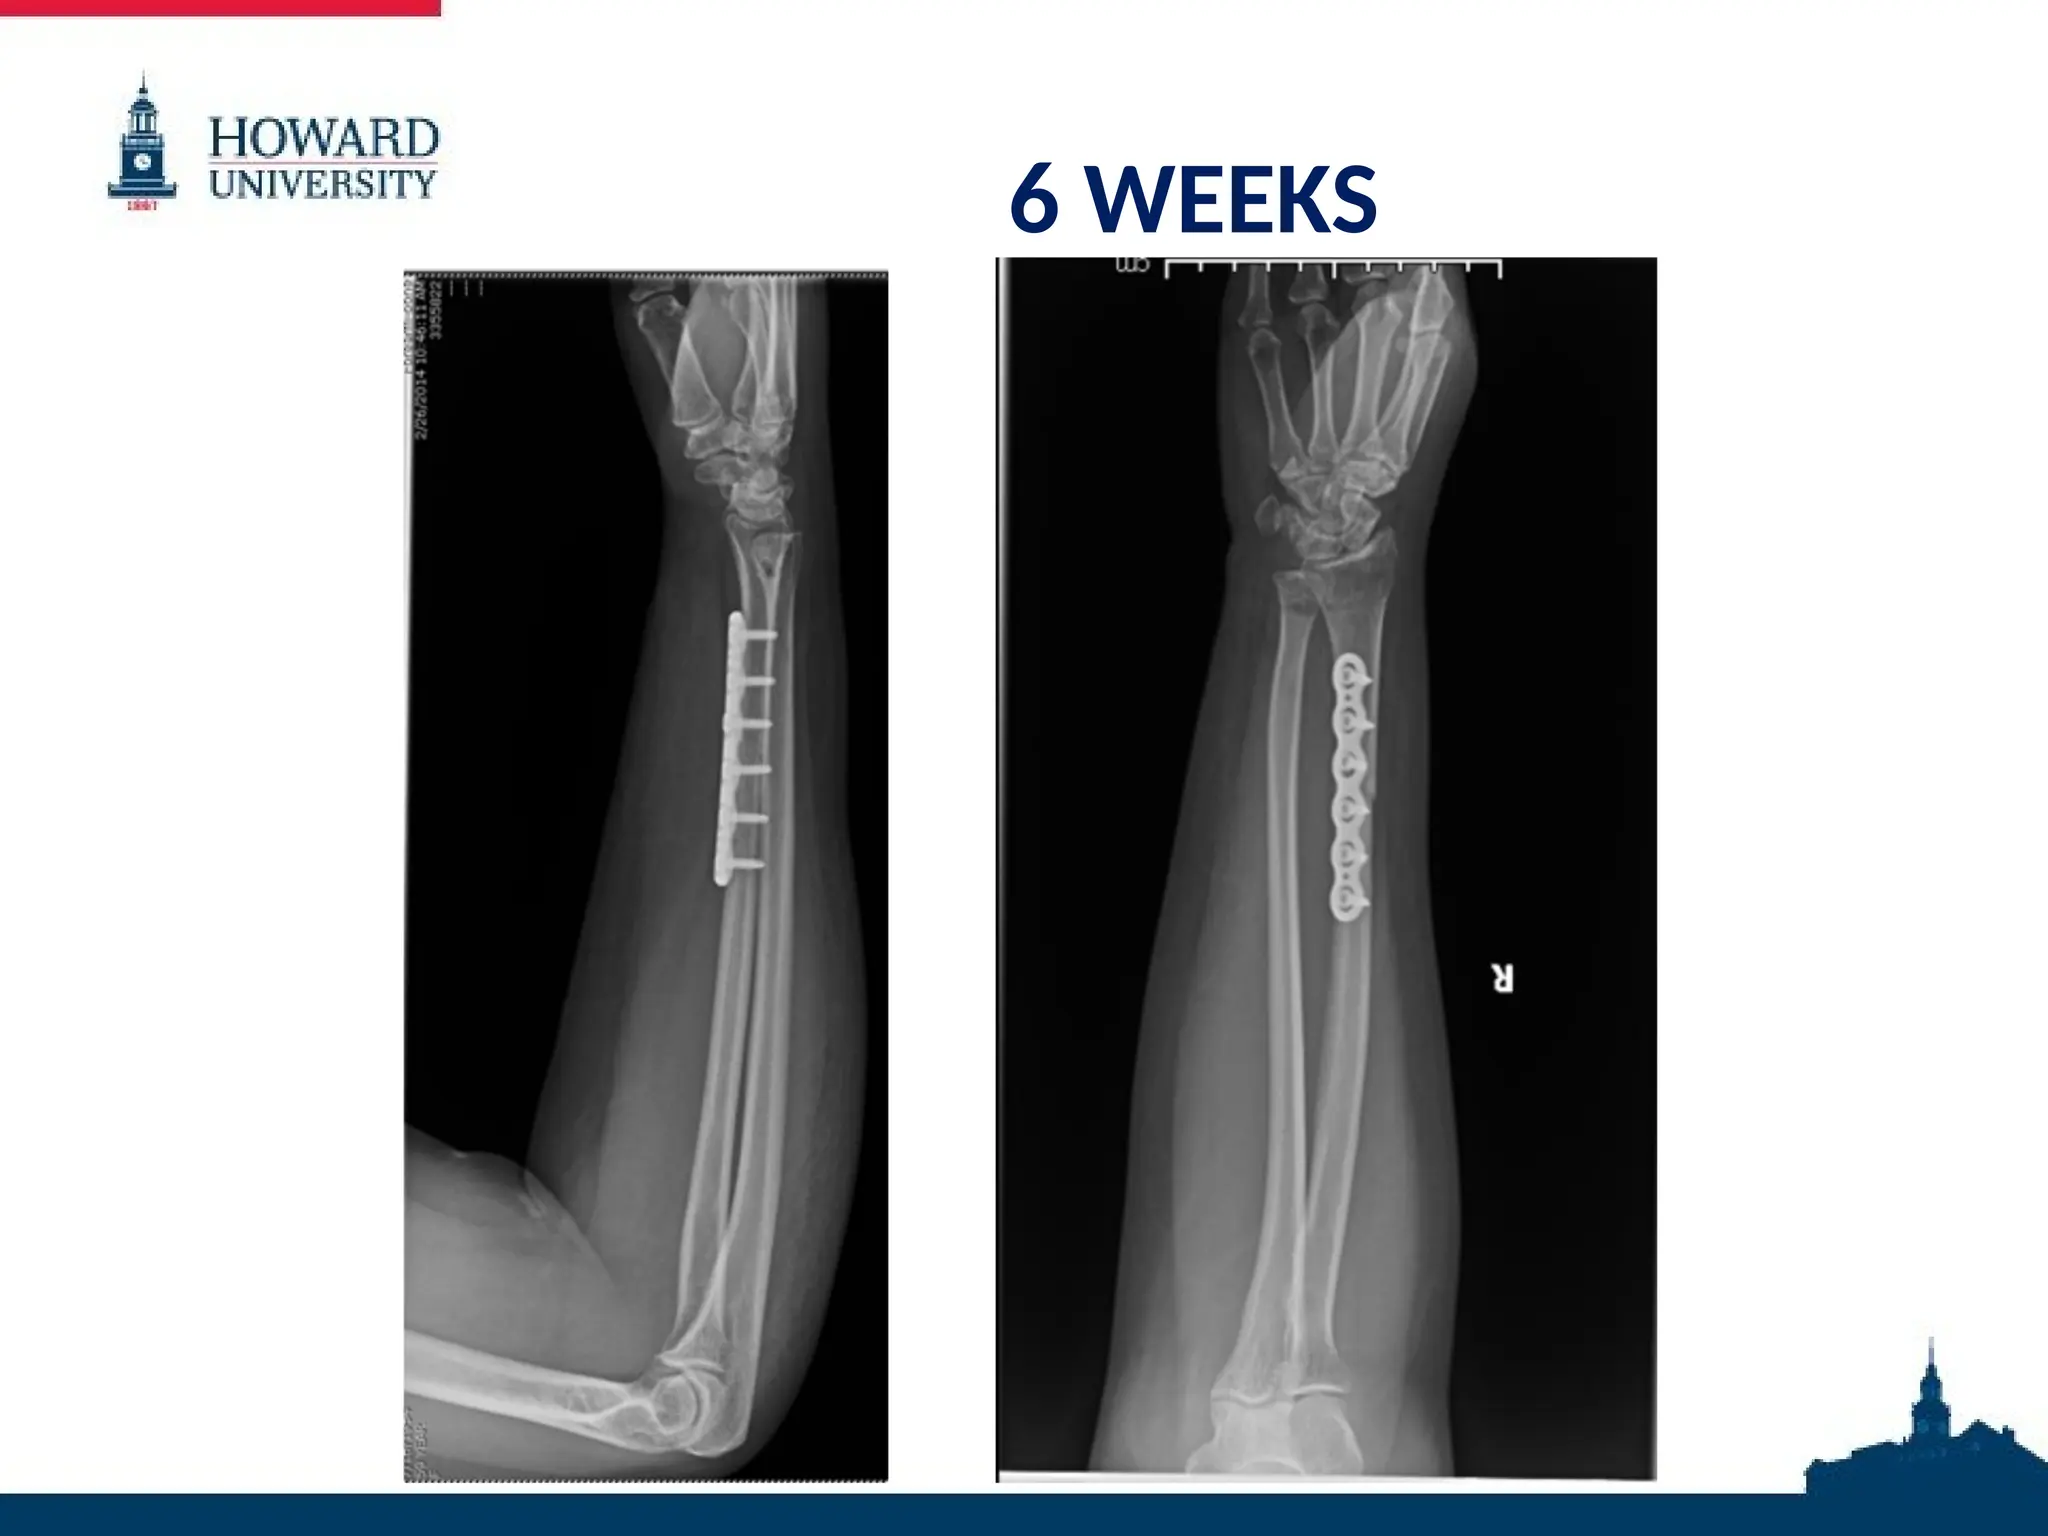

6 WEEKS

6 WEEKS • Incisionhealed • Cast removed • Pin removed • OT for ROM and strengthening begun